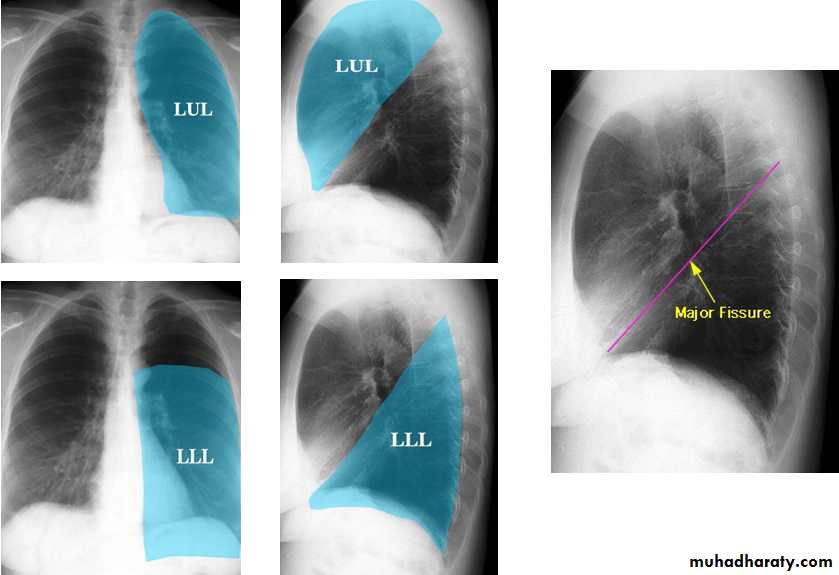

Lobes and fissures

This cut-out of a lateral chest x-ray shows the positions of the lobes of the right lung

On the left the oblique fissure is in a similar position but there is usually no horizontal fissure, and so there are only two lobes on the left.

Radiologic anatomy of the RT lung lobes

Radiologic anatomy of the LT lung lobes